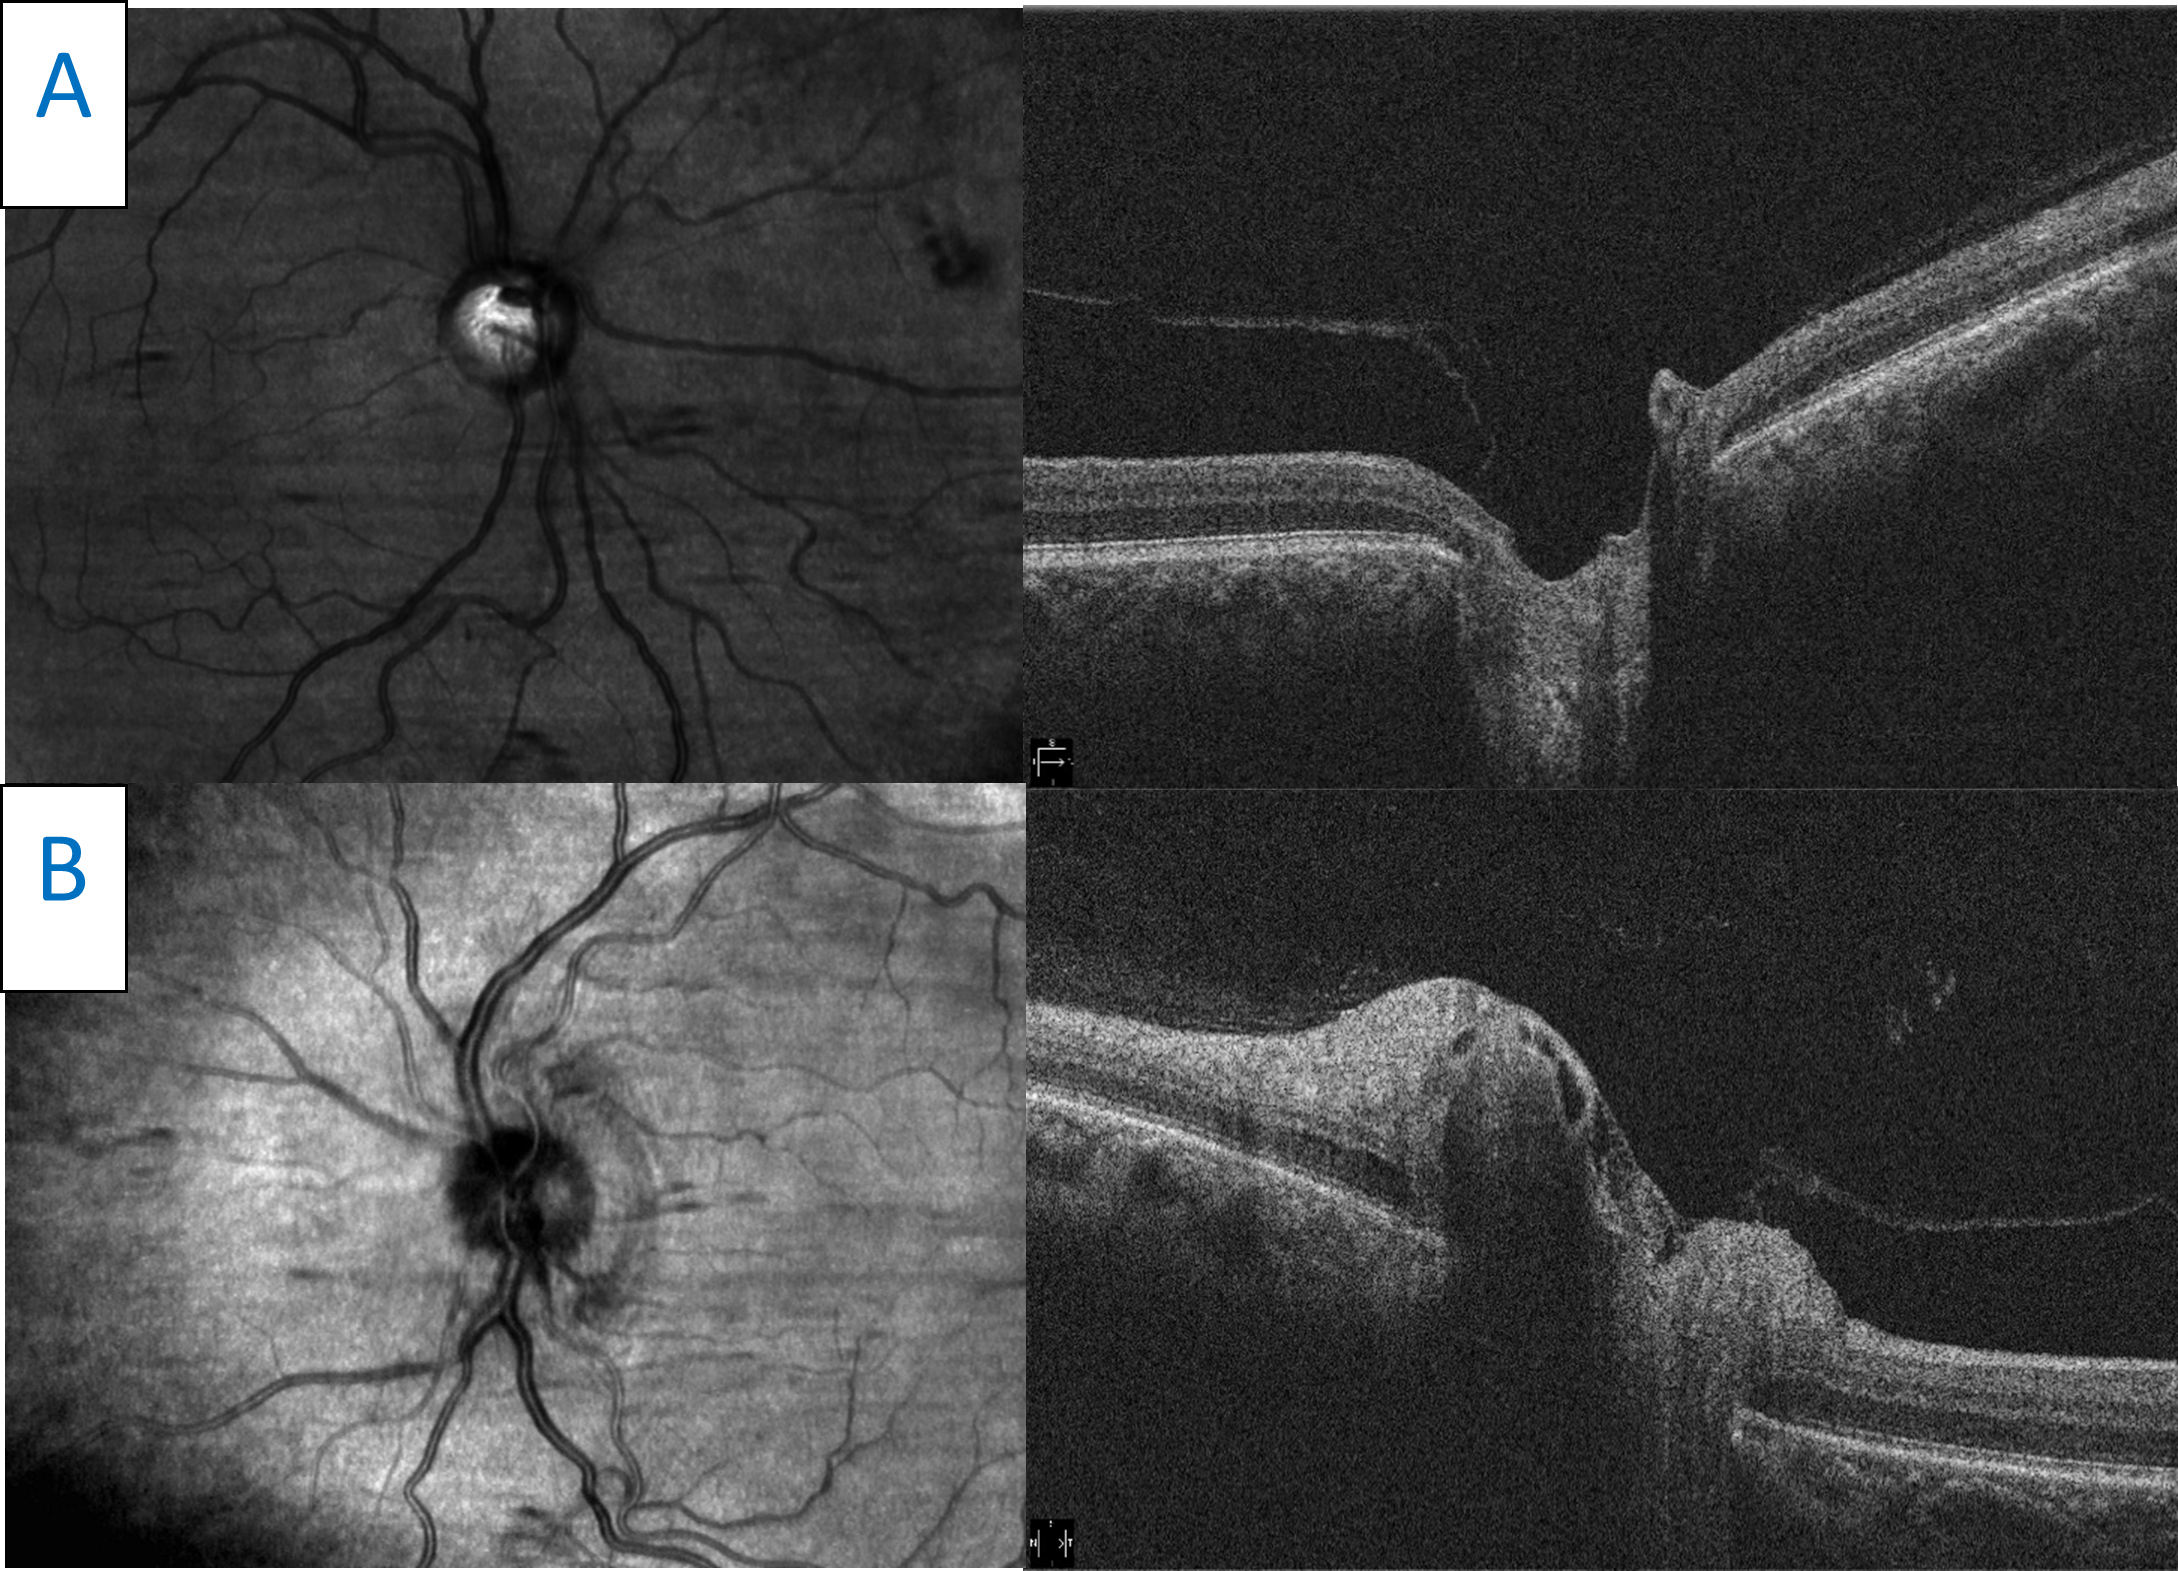

The patient was lost to follow-up but presented again 7 years later complaining of similar painful vision loss, this time in the left eye, for 1 to 2 weeks. Her entering visual acuity was 20/20 OD and 20/60 OS with a 1+ RAPD in the left eye. Entrance testing was otherwise unremarkable. Slit lamp examination was also unremarkable. IOP measured 19 mmHg in the right eye and 18 mmHg in the left eye. Dilated fundus examination revealed generalized optic disc pallor in the right eye. The pallor corresponded to the patient’s history of ON. Examination of the left eye revealed an edematous and hyperemic optic nerve. Cup to disc ratios were stable compared with previous exams. OCT raster scans showed a flat optic nerve in the right eye and nasal elevation and edema of the left optic nerve (Figure 6). Optic nerve head OCT of the right eye showed advanced, generalized thinning of both the GCC and RNFL (Figure 7). This correlated with the patient’s history of ON and her optic nerve presentation (pallor). Optic nerve head OCT scanning of the left eye revealed significant RNFL thickening combined with an inferior-temporal zone of GCC thinning (Figure 7). A recurrence of ON was suspected and repeat MRI of the brain and orbits was performed with and without contrast. The results were essentially normal with patchy, longitudinal enhancement of the left intraorbital segment of the optic nerve (Figure 8). AQP4-IgG and myelin oligodendrocyte glycoprotein (MOG) antibody testing was performed and showed positive anti-MOG titers. A diagnosis of MOGAD ON was established and the patient was treated with pulsed intravenous methylprednisolone followed by an oral prednisone taper. Follow-up visits showed rapid improvement of vision to 20/25 in the left eye in the presence of resultant disc pallor. No RAPD was noted. Repeat OCT showed stable findings of advanced and generalized thinning of both the GCC and RNFL in the right eye. OCT of the left eye showed advanced and generalized thinning of both the GCC and RNFL, which corresponded to the new disc pallor (Figure 9). In the next 2 years, the patient experienced several episodes of ON involving both the right and left eye. With each relapse, she reported rapid vision improvement following treatment with intravenous steroids. She was subsequently placed on maintenance therapy with oral MMF and her condition has remained stable with no further recurrences.

![]() Figure 7. A: Retinal nerve fiber layer (RNFL) analysis of both eyes. In the right eye, advanced RNFL thinning, sparing the nasal portion of the nerve, is seen. Compared with the previous scans (Figure 5), progression is illustrated by a lower average thickness and deeper and larger amounts of thinning on the deviation map. Analysis of the left eye shows acute RNFL thickening, greater superiorly than inferiorly, which was not noted in the previous scans (Figure 5). B: Ganglion cell analysis of both eyes. Advanced ganglion cell complex (GCC) thinning is present in the right eye. This corresponds with the patient’s previous bout of optic neuritis. Compared with previous scans (Figure 5), progressive GCC thinning is illustrated in the right eye by a lower average GCC thickness. Inferior-temporal GCC thinning is noted in the left eye. The scan is relatively stable when compared with the previous scan (Figure 5). |

![]() Figure 9. Panomap analysis showing advanced, bilateral thinning of the retinal nerve fiber layer and ganglion cell complex. These findings correspond to the bilateral disc pallor observed on fundus examination. Click to enlarge |